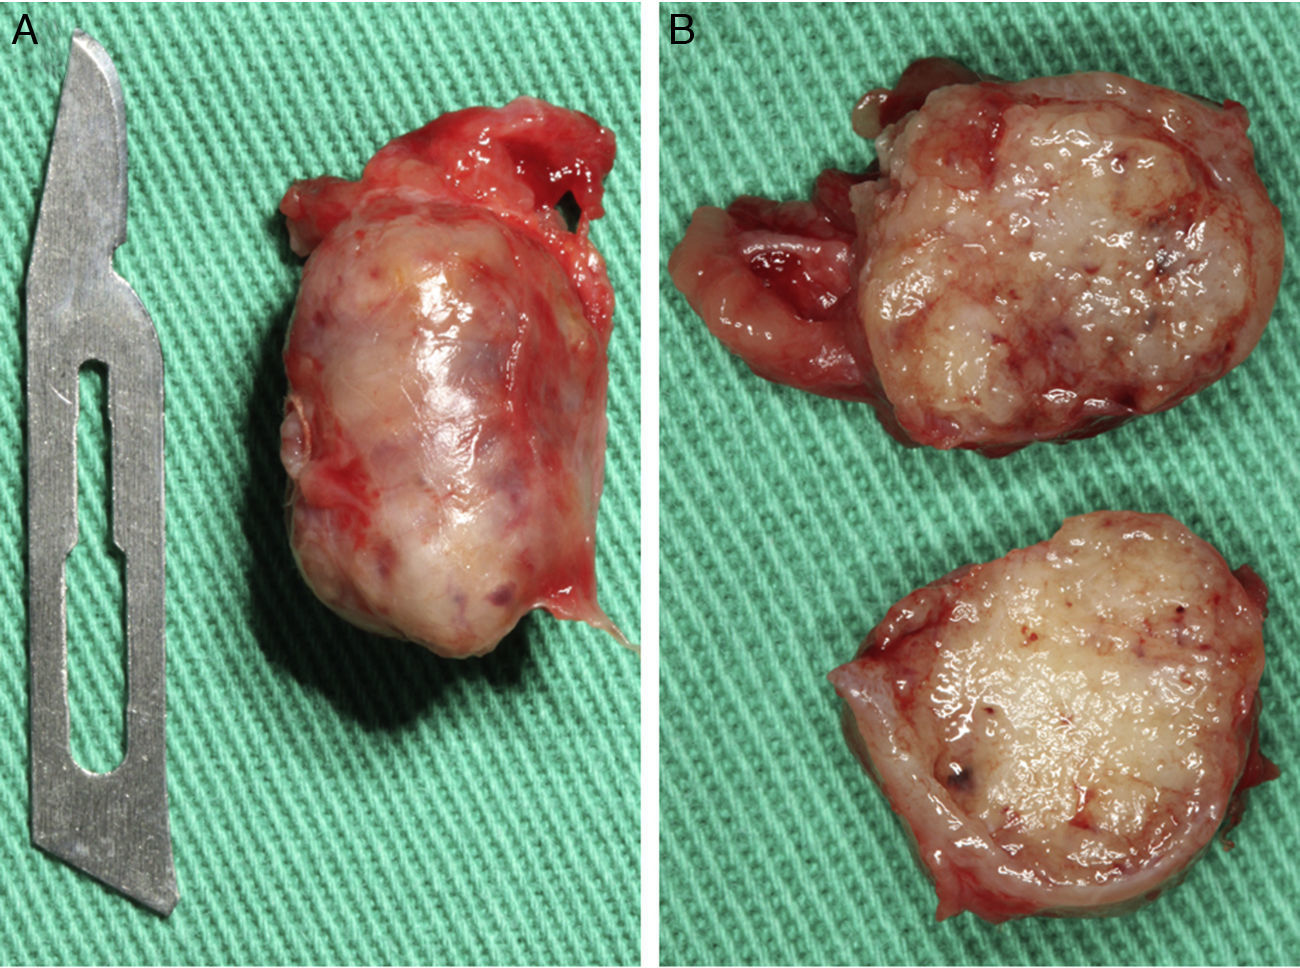

Casos clínicosCaso 1Paciente do sexo masculino, 68 anos de idade, leucoderma, procurou a Clínica de Estomatologia do Departamento de Odontologia da Pontifícia Universidade Católica de Minas Gerais (PUC Minas) queixando‐se de aumento de volume no palato, com tempo de evolução de 2 anos e discreta sintomatologia dolorosa. A anamnese não revelou alterações sistémicas. Ao exame clínico extraoral não foram observadas alterações. O exame clínico intraoral mostrou lesão nodular, pediculada, de consistência firme, localizada no palato duro do lado direito, entre os pré‐molares superiores e a rafe palatina, medindo aproximadamente 2cm na sua maior extensão. Foi realizada uma radiografia oclusal de maxila que não mostrou alterações ósseas. As hipóteses diagnósticas de neoplasia de glândula salivar e neoplasia mesenquimal benigna foram consideradas. Foi realizada biópsia incisional com diagnóstico anatomopatológico de adenoma pleomórfico. O tratamento proposto para a lesão foi a remoção cirúrgica conservadora. Paciente retornou após 4 semanas exibindo, ao exame intraoral, ulcerações na mucosa que recobria a lesão (fig. 1). Inicialmente, foi realizada anestesia local por meio da técnica supraperiosteal para bloqueio de ramos do nervo palatino maior, com cloridrato de lidocaína 2% e epinefrina 1:100.000 (ALPHACAINE 100®, DFL, Rio de Janeiro, Brasil). Em seguida, foi realizada incisão na base da lesão com bisturi lâmina 15 (Solidor, São Paulo, Brasil) e, após o descolamento do retalho mucoso palatino, a lesão foi exposta e removida (fig. 2). Foi realizada limpeza da ferida cirúrgica e sutura com fio seda Ethicon™ 4.0 (Johnson & Johnson, São Paulo, Brasil) (fig. 3). A lesão excisada (fig. 4) foi fixada em solução de formaldeído a 10% e enviada para exame anatomopatológico no Laboratório de Patologia Bucal da PUC Minas.

Paciente do sexo feminino, 31 anos de idade, leucoderma, foi encaminhada pelo cirurgião‐dentista à Clínica de Estomatologia do Departamento de Odontologia da PUC Minas para avaliação de lesão nodular no palato duro com diagnóstico histopatológico de adenoma pleomórfico, obtido por meio de biópsia incisional. Durante a anamnese, a paciente relatou a evolução da lesão há 4 anos com característica assintomática. Relatou estar no sexto mês de gestação e não apresentava outras alterações sistémicas. O exame extraoral mostrou ausência de alterações. Ao exame intraoral, observou‐se um aumento de volume bem delimitado no palato duro do lado direito, de consistência firme e coloração semelhante à da mucosa normal, medindo aproximadamente 2,5cm, exibindo pequena área de ulceração no local da realização da biópsia incisional (fig. 9). O exame radiográfico não mostrou alterações. O tratamento proposto foi a remoção cirúrgica conservadora e confecção de placa palatina em acrílico com grampos retentores para minimizar o desconforto pós‐operatório. Foi realizada anestesia local com lidocaína 2% e epinefrina 1:100.000 (ALPHACAINE 100®, DFL, Rio de Janeiro, Brasil), seguida de incisão semilunar com bisturi lâmina 15 (Solidor, São Paulo, Brasil) e rebatimento do retalho mucoso. Como a lesão se apresentava encapsulada, foi possível destacá‐la da mucosa suprajacente com facilidade (fig. 10). O retalho foi reposicionado por meio de pontos isolados (fig. 11) e a lesão (fig. 12) foi fixada em formaldeído a 10% para realização de exame anatomopatológico no Laboratório de Patologia Bucal da PUC Minas. Em seguida, foi colocada a placa de acrílico (fig. 13) para proteção da região operada e controlo da sintomatologia dolorosa.